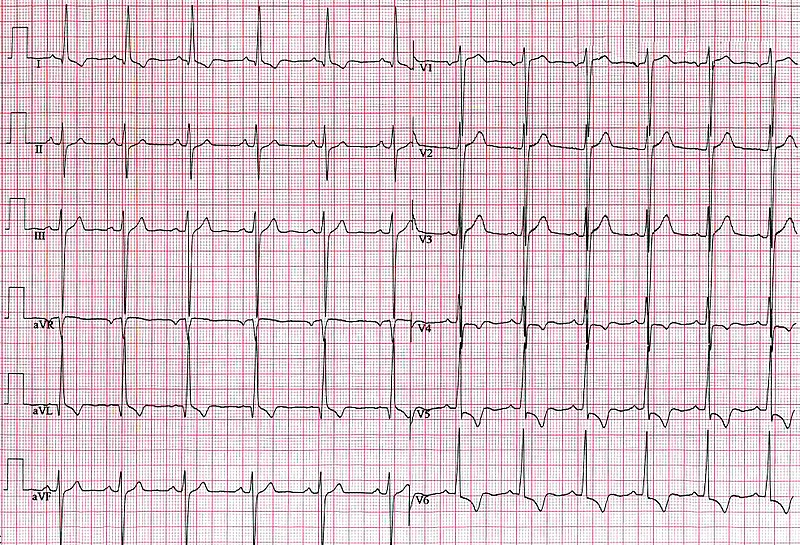

E-Echocardiogram (ECG) with PR prolongation